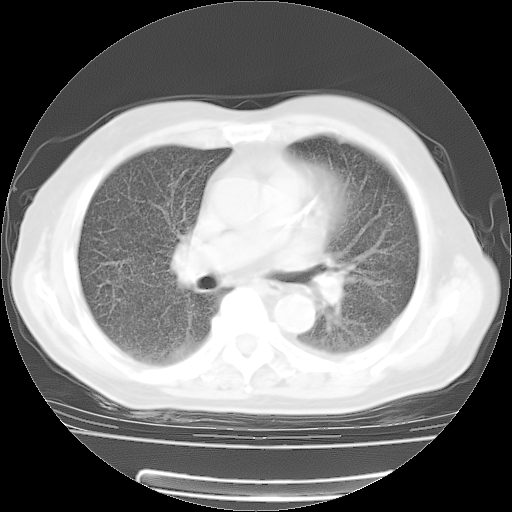

4月14日肺部CT

23.JPG

24.JPG

25.JPG

26.JPG

肺部CT平扫未见异常。